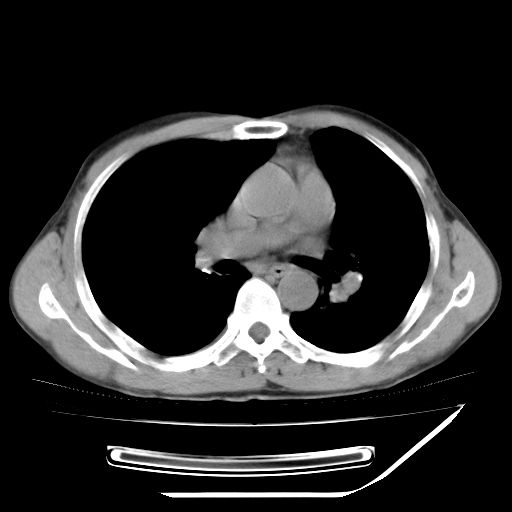

男,59岁,“结核性胸膜炎”30余年,胸部经常疼痛,多次x检查提示“肺部”炎症。腹部疼痛5日,b超提示:“肝内短管结石,余显示不清,建议进一步检查。”

两肺结核并右侧胸腔积液;脾脏、腹腔及腹膜后淋巴结结核[陈旧性];肝内胆管结石

胸部腹部都是结核(双肺。纵隔淋巴结,肝脏,脾脏,肠系膜)

两肺结核并右侧胸腔积液;脾脏、腹腔及腹膜后淋巴结结核[陈旧性];肝内胆管结石。直肠息肉?